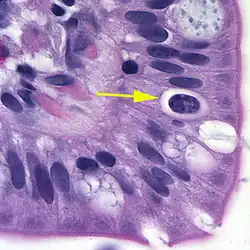

| Oocyst in epithelial cyst of mammalian host | |

The coccidian parasite Cystoisospora belli infects the epithelial cells of the small intestine, and is the least common of the three intestinal coccidia that infect humans (Toxoplasma, Cryptosporidium, and Cystoisospora).

At time of excretion, the immature oocyst usually contains one sporoblast (more rarely two). In further maturation after excretion, the sporoblast divides in two, so the oocyst now contains two sporoblasts. The sporoblasts secrete a cyst wall, thus becoming sporocysts; and the sporocysts divide twice to produce four sporozoites each. Infection occurs by ingestion of sporocyst-containing oocysts: the sporocysts excyst in the small intestine and release their sporozoites, which invade the epithelial cells and initiate schizogony. Upon rupture of the schizonts, the merozoites are released, invade new epithelial cells, and continue the cycle of asexual multiplication. Trophozoites develop into schizonts which contain multiple merozoites. After a minimum of one week, the sexual stage begins with the development of male and female gametocytes. Fertilization results in the development of oocysts that are excreted in the stool. Cystoisospora belli infects both humans and animals.

Microscopic demonstration of the large typically shaped oocysts is the basis for diagnosis. Because the oocysts may be passed in small amounts and intermittently, repeated stool examinations and concentration procedures are recommended. If stool examinations are negative, examination of duodenal specimens by biopsy or string test (Enterotest) may be needed. The oocysts can be visualized on wet mounts by microscopy with bright-field, differential interference contrast (DIC), and epifluorescence. They can also be stained by modified acid-fast stain.